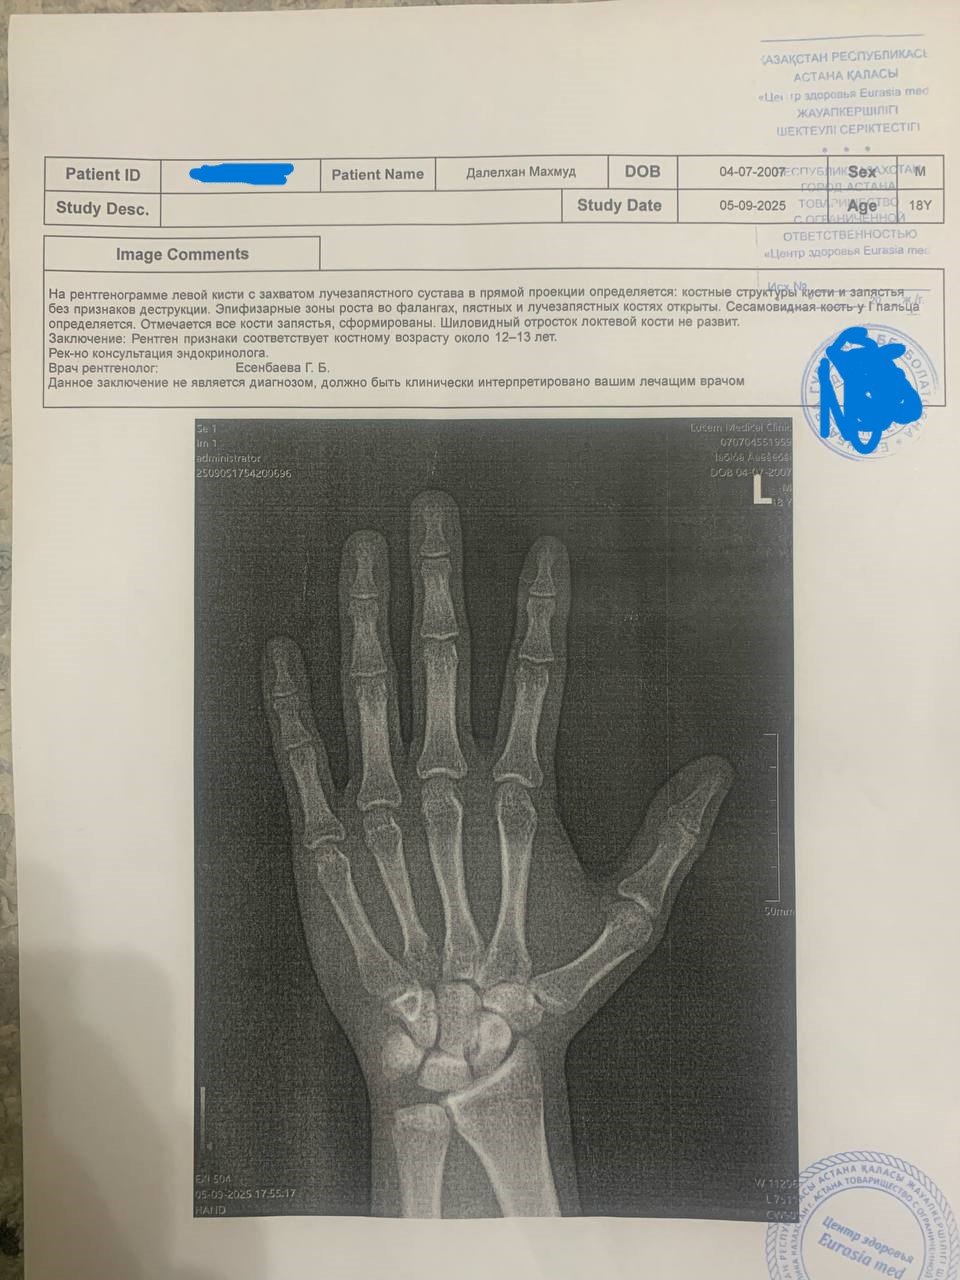

so i did the xray of my left wrist and i found out that my bone age is 12-13 when my chronological age is 18 and the growth plates are open but im not sure how wide open they are. could the bone age mean that i still have 3-4 years of growth? i turned 18 this summer my current height is 160cm. i have not grown a single centimeter since 7th grade and i hope hgh will make me 10-15cm taller im on 4ius ed and soon will up the dosage to 6ius and im planning on running hgh a whole year